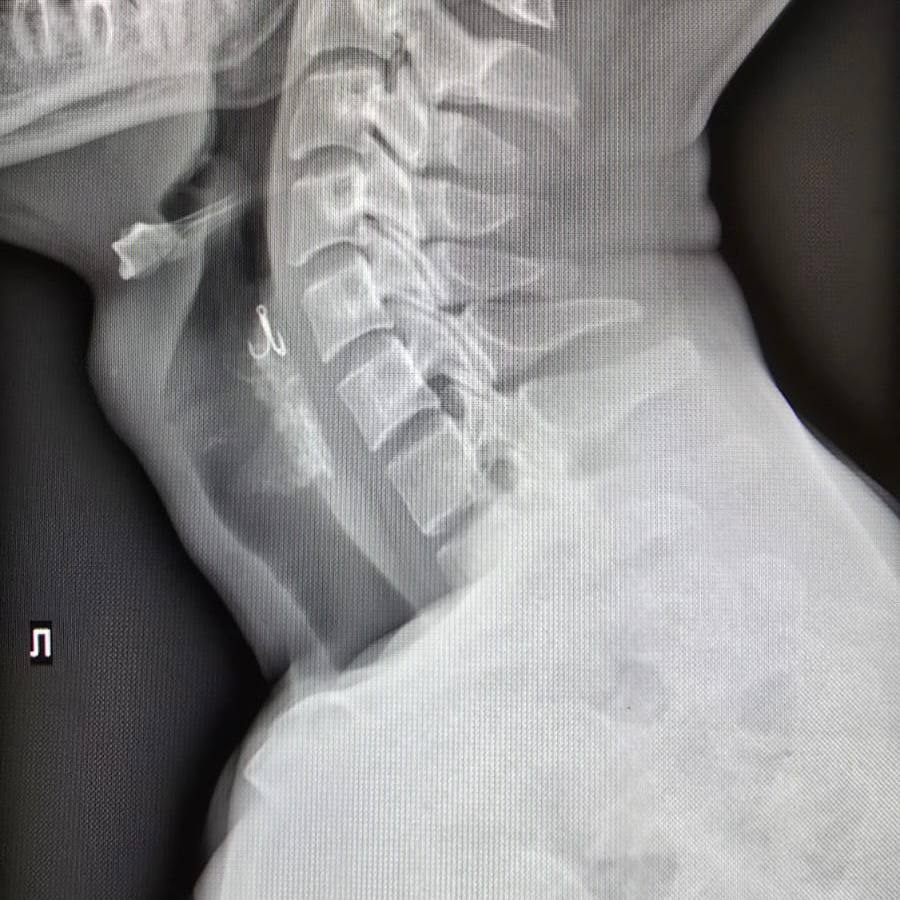

В Красноярской больнице ему выполнили рентгенографию, которая показала, что крючок застрял в стенке глотки. Это угрожало серьезными повреждениями тканей и развитием воспаления. Мужчине требовалась операция.